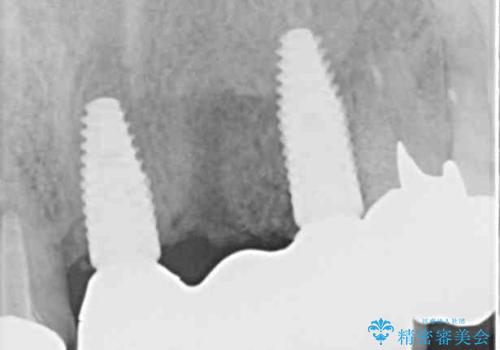

抜歯する歯の両隣も治療が必要と思える歯であったため、広範囲なオールセラミックブリッジによる治療も提案しましたが、患者様本人の希望もあってインプラント2本による欠損部のみのブリッジ治療を行うこととしました。

歯の破折による抜歯のため、歯槽骨の欠損が大きく、骨造成処置の併用が必要であり、骨造成が落ち着くまでに半年ほど時間を要することになります。

2本同時に抜去して一時的な入れ歯の使用を提案しましたが、極力固定式の仮歯を使用したいとのことで、半年に1本ずつ埋入することとし、トータルで1年強を要する治療計画となりました。

治療により前歯は非常に安定しましたが、インプラント部の両隣、特に反対側の前歯はクラウンのやり直しが必要な状態であったので、今後反対側の治療も実施していく予定です。